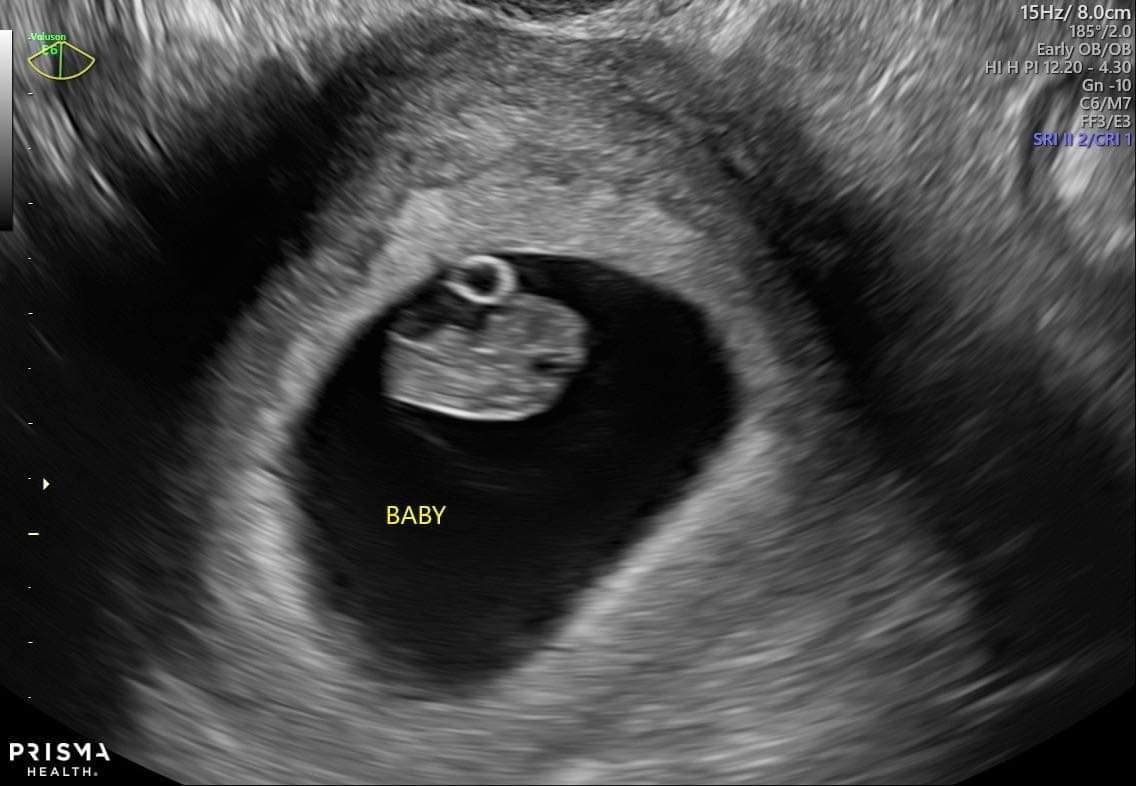

Had my first US at 5w2d as my obgyn was suspecting an ectopic pregnancy due my history of loss. Saw a gestational sac and yolk sac no fetal pole tough! I have my next US up at week 7. So nervous!